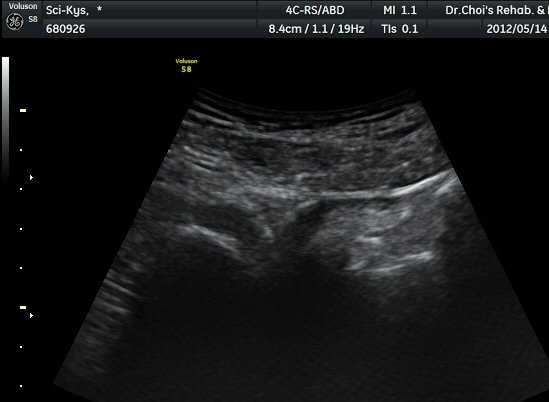

ŽÃËÀÚ¸¦ ¾à°£ ±ÙÀ§ºÎ·Î À̵¿ÇÏ´Ï °æ°è°¡ ºÒºÐ¸íÇÑ »À°¡ Á°ñ½Å°æ ¿ÜÃø¿¡¼­ µ¹ÃâÇϸ鼭

Á°ñ½Å°æÀ» ³»ÃøÀ¸·Î ½ÉÇÏ°Ô ÀüÀ§½ÃŲ´Ù(±×¸² 4, 5).